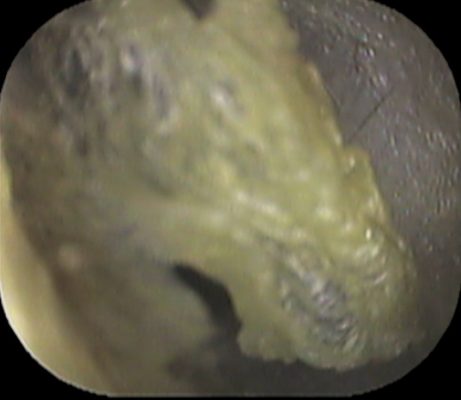

続いて左耳

何か 動物のようにも見えました

何かと言いますと↓

プードルです